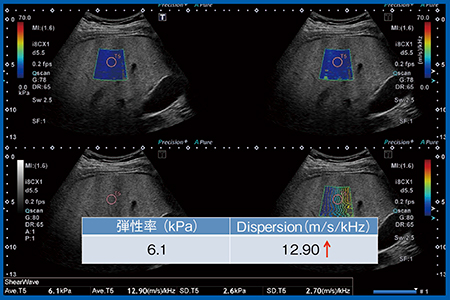

症例2(図9)はNASH症例で,脂肪肝が比較的進行している。弾性率は6.1kPaと若干上がるが,この程度であれば正常範囲である。それに比して,Dispersion slopeは12.9m/s/kHzと上昇傾向が見られた。

図9 症例2:NASH症例の弾性率とDispersion slope

Plt 24.8万,AST 78,ALT 172,T-Bil 0.42